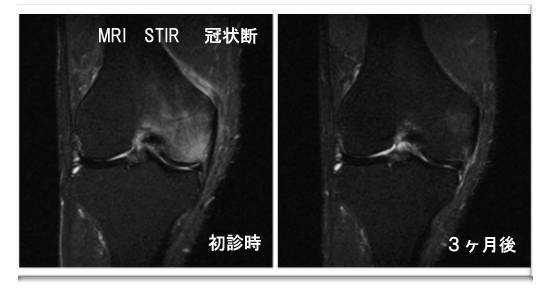

また、MRI検査などを併用して、どの程度リウマチが原因なのか、それとも骨壊死症、PVSなどの腫瘍性疾患、軟骨軟化症、半月板の加齢による亀裂が原因なのかを診断します。

膝関節骨壊死症

最近の多くの研究の結果、膝関節骨壊死の本質は軟骨下骨挫傷による二次性におこる骨壊死であろうと考えられるようになりました。半月板の亀裂や「ずれ」のために膝の上の骨と下の骨がギシッとこすれあい骨の表面にひびがはいる、というのが大半の膝関節骨壊死の原因だと考えています。